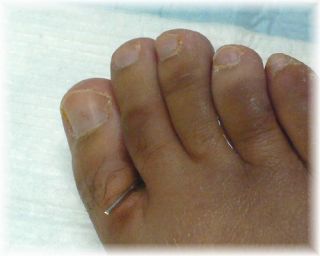

事故当日。

腫れています。外傷はありません。